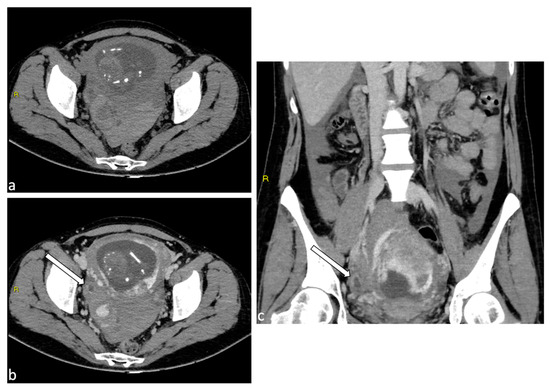

Uterine rupture is a rare and potentially fatal obstetric complication defined as a full thickness tear of the uterine wall, typically occurring during labor or delivery. The most common etiological factor is a previous uterine scar, often resulting from a previous cesarean section [77]. Other risk factors include a history of uterine surgery, trauma, or congenital uterine anomalies. Uterine rupture may manifest as sudden and severe abdominal pain, vaginal bleeding and hemoperitoneum rapidly progressive to maternal shock. US in the initial evaluation may show an abnormality in the uterine wall, a hematoma next to a hysterotomy scar, free fluid in the peritoneum, or fetal parts outside the uterus [78] (Figure 8). Uterine rupture necessitates immediate surgical intervention, often requiring an emergency cesarean section.

Figure 8.

Uterine rupture. A 39-year-old female patient with a history of laparoscopic myomectomy who was pregnant at 29 weeks presented to the emergency department with abdominal pain and vaginal bleeding. Transabdominal ultrasound demonstrated hemoperitoneum (a) and a live fetus. CT scan without contrast medium (axial, b; sagittal, c) was performed urgently with confirmation of abundant hemoperitoneum. An urgent caesarean section was performed, with evidence of uterine rupture at the posterior wall in the presence of placenta accreta. Hysterectomy was performed.